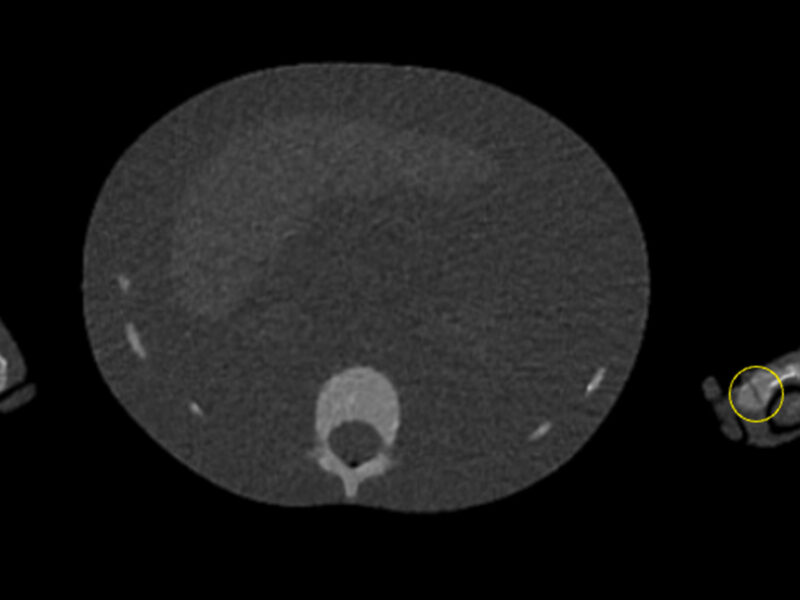

Une étude évalue les capacités des MERM à détecter des fractures au scanner basse dose

Des chercheurs australiens ont évalué l'aptitude des MERM à identifier des fractures sur un fantôme pédiatrique en scanner basse dose. Les participants ont bien détectées celles du crâne et du tibia, moins bien ...